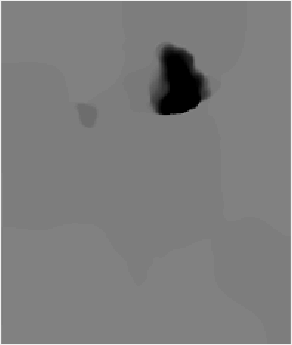

Fig. 3: Example atlas-to-image registration errors [mm]: (a) tumor; (b) LRS; (c) PCA model w/o regularization; (d) PCA model w/ one step of regularization; (e) PCA model w/ two steps of regularization.

Fig. 2 shows atlas-to-image registration results for images with and without tumor, LRS reconstruction and our PCA-based models with and without regularization. Fig. 3 shows the spatial error distributions, compared to the ground truth registration. We use NiftyReg [17] (with standard settings) and NCC for registrations. Errors are computed using Euclidean distance. Direct registration of the tumor image results in large registration errors. Registration to the low-rank reconstruction greatly reduces the error in the tumor areas but retains errors near the cortex, mainly due to its blurry reconstruction. Our PCA models further reduce registration errors in the tumor areas and keep errors near the cortex low.